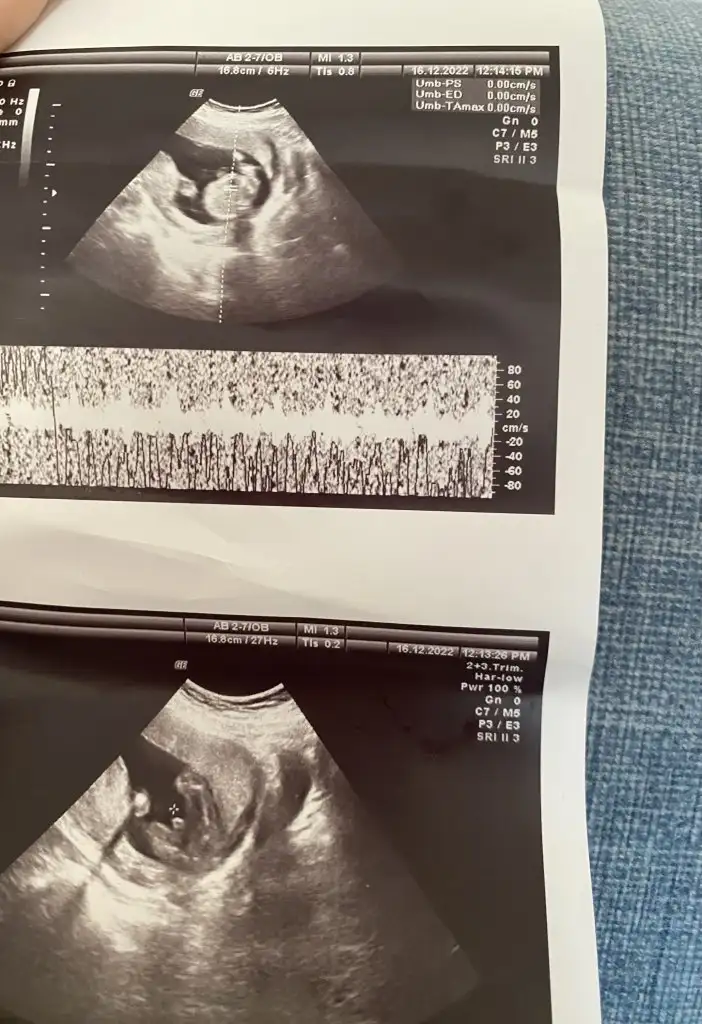

bize de erkek dedi 16, haftadayız sizce yanılma payı olabilir mi ikinci fotoğraftaki organı mı acaba

İkili testte 3. De ense ölçümü zor aldılar hareketli pozisyon vermedi 13. Haftada bir doktora gittim göstermedi sabahsi başka bir doktor bacak arasını gösterdi erkek büyük ihtimalle dedi dün 13 haftadaki ilk doktora gittim bacak arasından kordon geciyor cinsiyet görünmüyor cinsiyeti örtmüş tahminde bulunamam dedi bende bu defa acaba diğer doktorun gördüğü kordon muydu kordonu pipi mi zannetti diyorum çünkü bir tek o tahminde bulundu